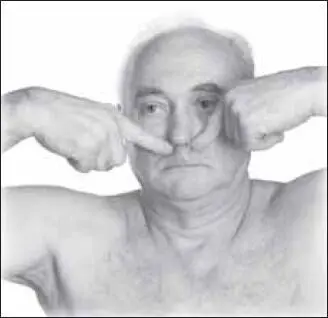

Чтобы предотвратить обморок, надо начинать с массажа точки жэнъ-чжун (расположена на средней линии лица в верхней трети желоба верхней губы) (рис. 135).

Воздействие стимулирующее, тонизирующее, возбуждающее (от 10–20 секунд). Чаще проводится 2-м пальцем (1-м и 3-м пальцем производят фиксацию тканей вокруг точки).

Далее массируют точки ди-цан (находятся по уголкам рта) (рис. 136).

Массируют одновременно обе симметрично расположенные точки. Воздействие короткое, быстрое, с усилием 2–3 кг (до 10–20 секунд). Этот вариант точечного массажа можно при необходимости повторять.

Следующая точка – чэн-цзянъ (она расположена под нижней губой во впадине, находящейся в центре подбородочной ямки) (рис. 137).

Известной «антистрессовой» точкой является точка ди-хэ (расположена в подбородочной ямке, при пальпации там чувствуется пульсация) (рис. 138).

Воздействие проводится чаще всего 1-м пальцем. Фиксируя точку концевой фалангой, производят резкое надавливание в течение 2–3 секунд. Действие повторяют по 10–15 раз, достигая эффекта расслабленности, релаксации.